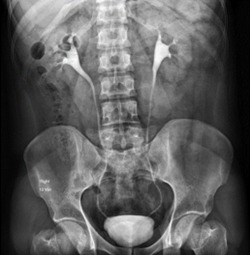

At Pulse Clinic, we are dedicated to providing comprehensive healthcare services that meet the diverse needs of our patients. With a team of highly skilled professionals and cutting-edge technology, we offer a wide range of medical services and diagnostic facilities to ensure your well-being. Here's an overview of the services we provide: